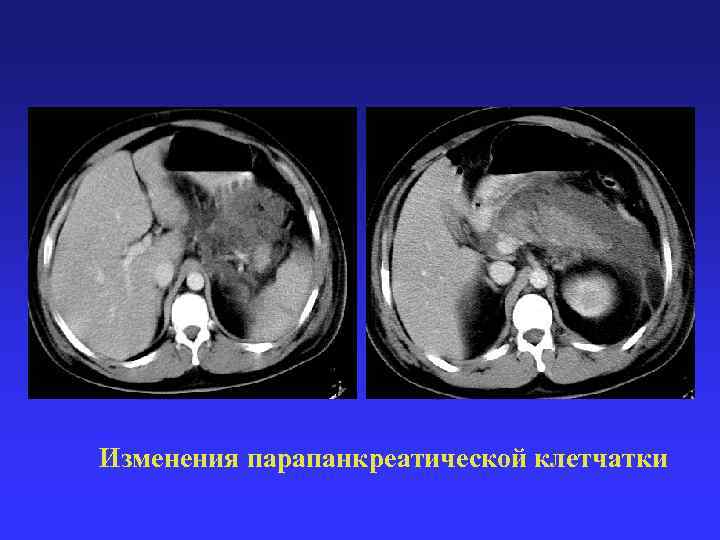

Качественные показатели: положение, форма, контуры, структура Количественные показатели: объем, размер, плотность Изменения в паренхиме Качественные показатели: положение, форма, контуры, структура Количественные показатели: объем, размер, плотность Изменения в паренхиме поджелудочной железы Изменения в парапанкреатической клетчатке

Изменения парапанкреатической клетчатки Изменения парапанкреатической клетчатки